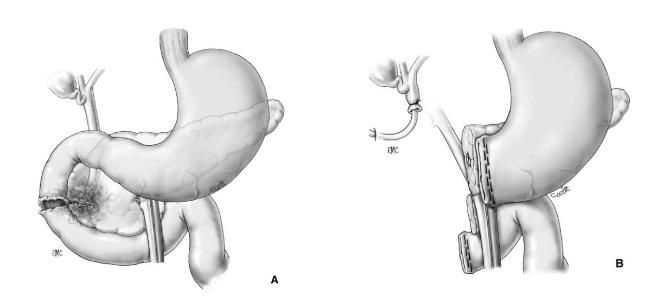

Phẫu thuật Patch tá tràng – Patch technique

A – Tổn thương rộng ở D2, lộ bóng Vater

B – Đưa quai hỗng tràng lên úp vào vết thương D2 kiểu Roux-en-Y

Phẫu thuật cắt bỏ một phần tá tràng

A- Vỡ D3 độ III (AAST) ngay sát bó mạch mạc treo tràng trên

B- Cắt đoạn D4, nối hỗng tràng với D2 Roux-en-Y